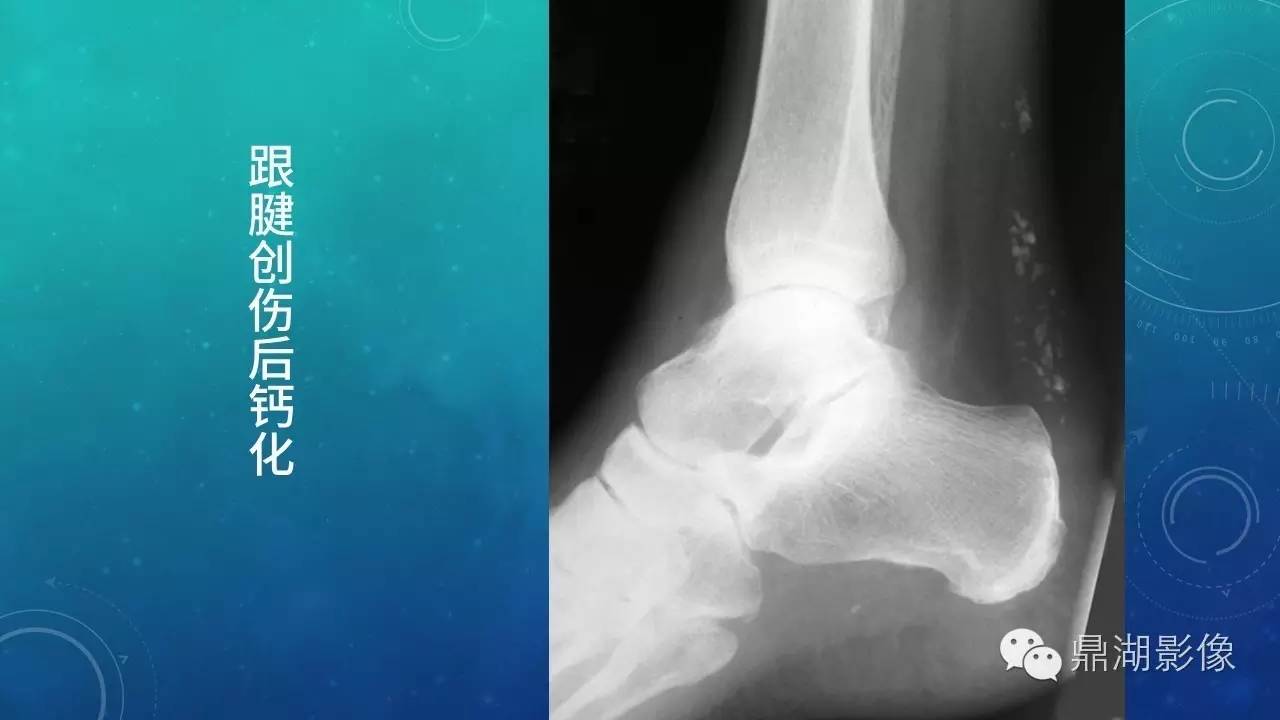

软组织钙化(的鉴别)